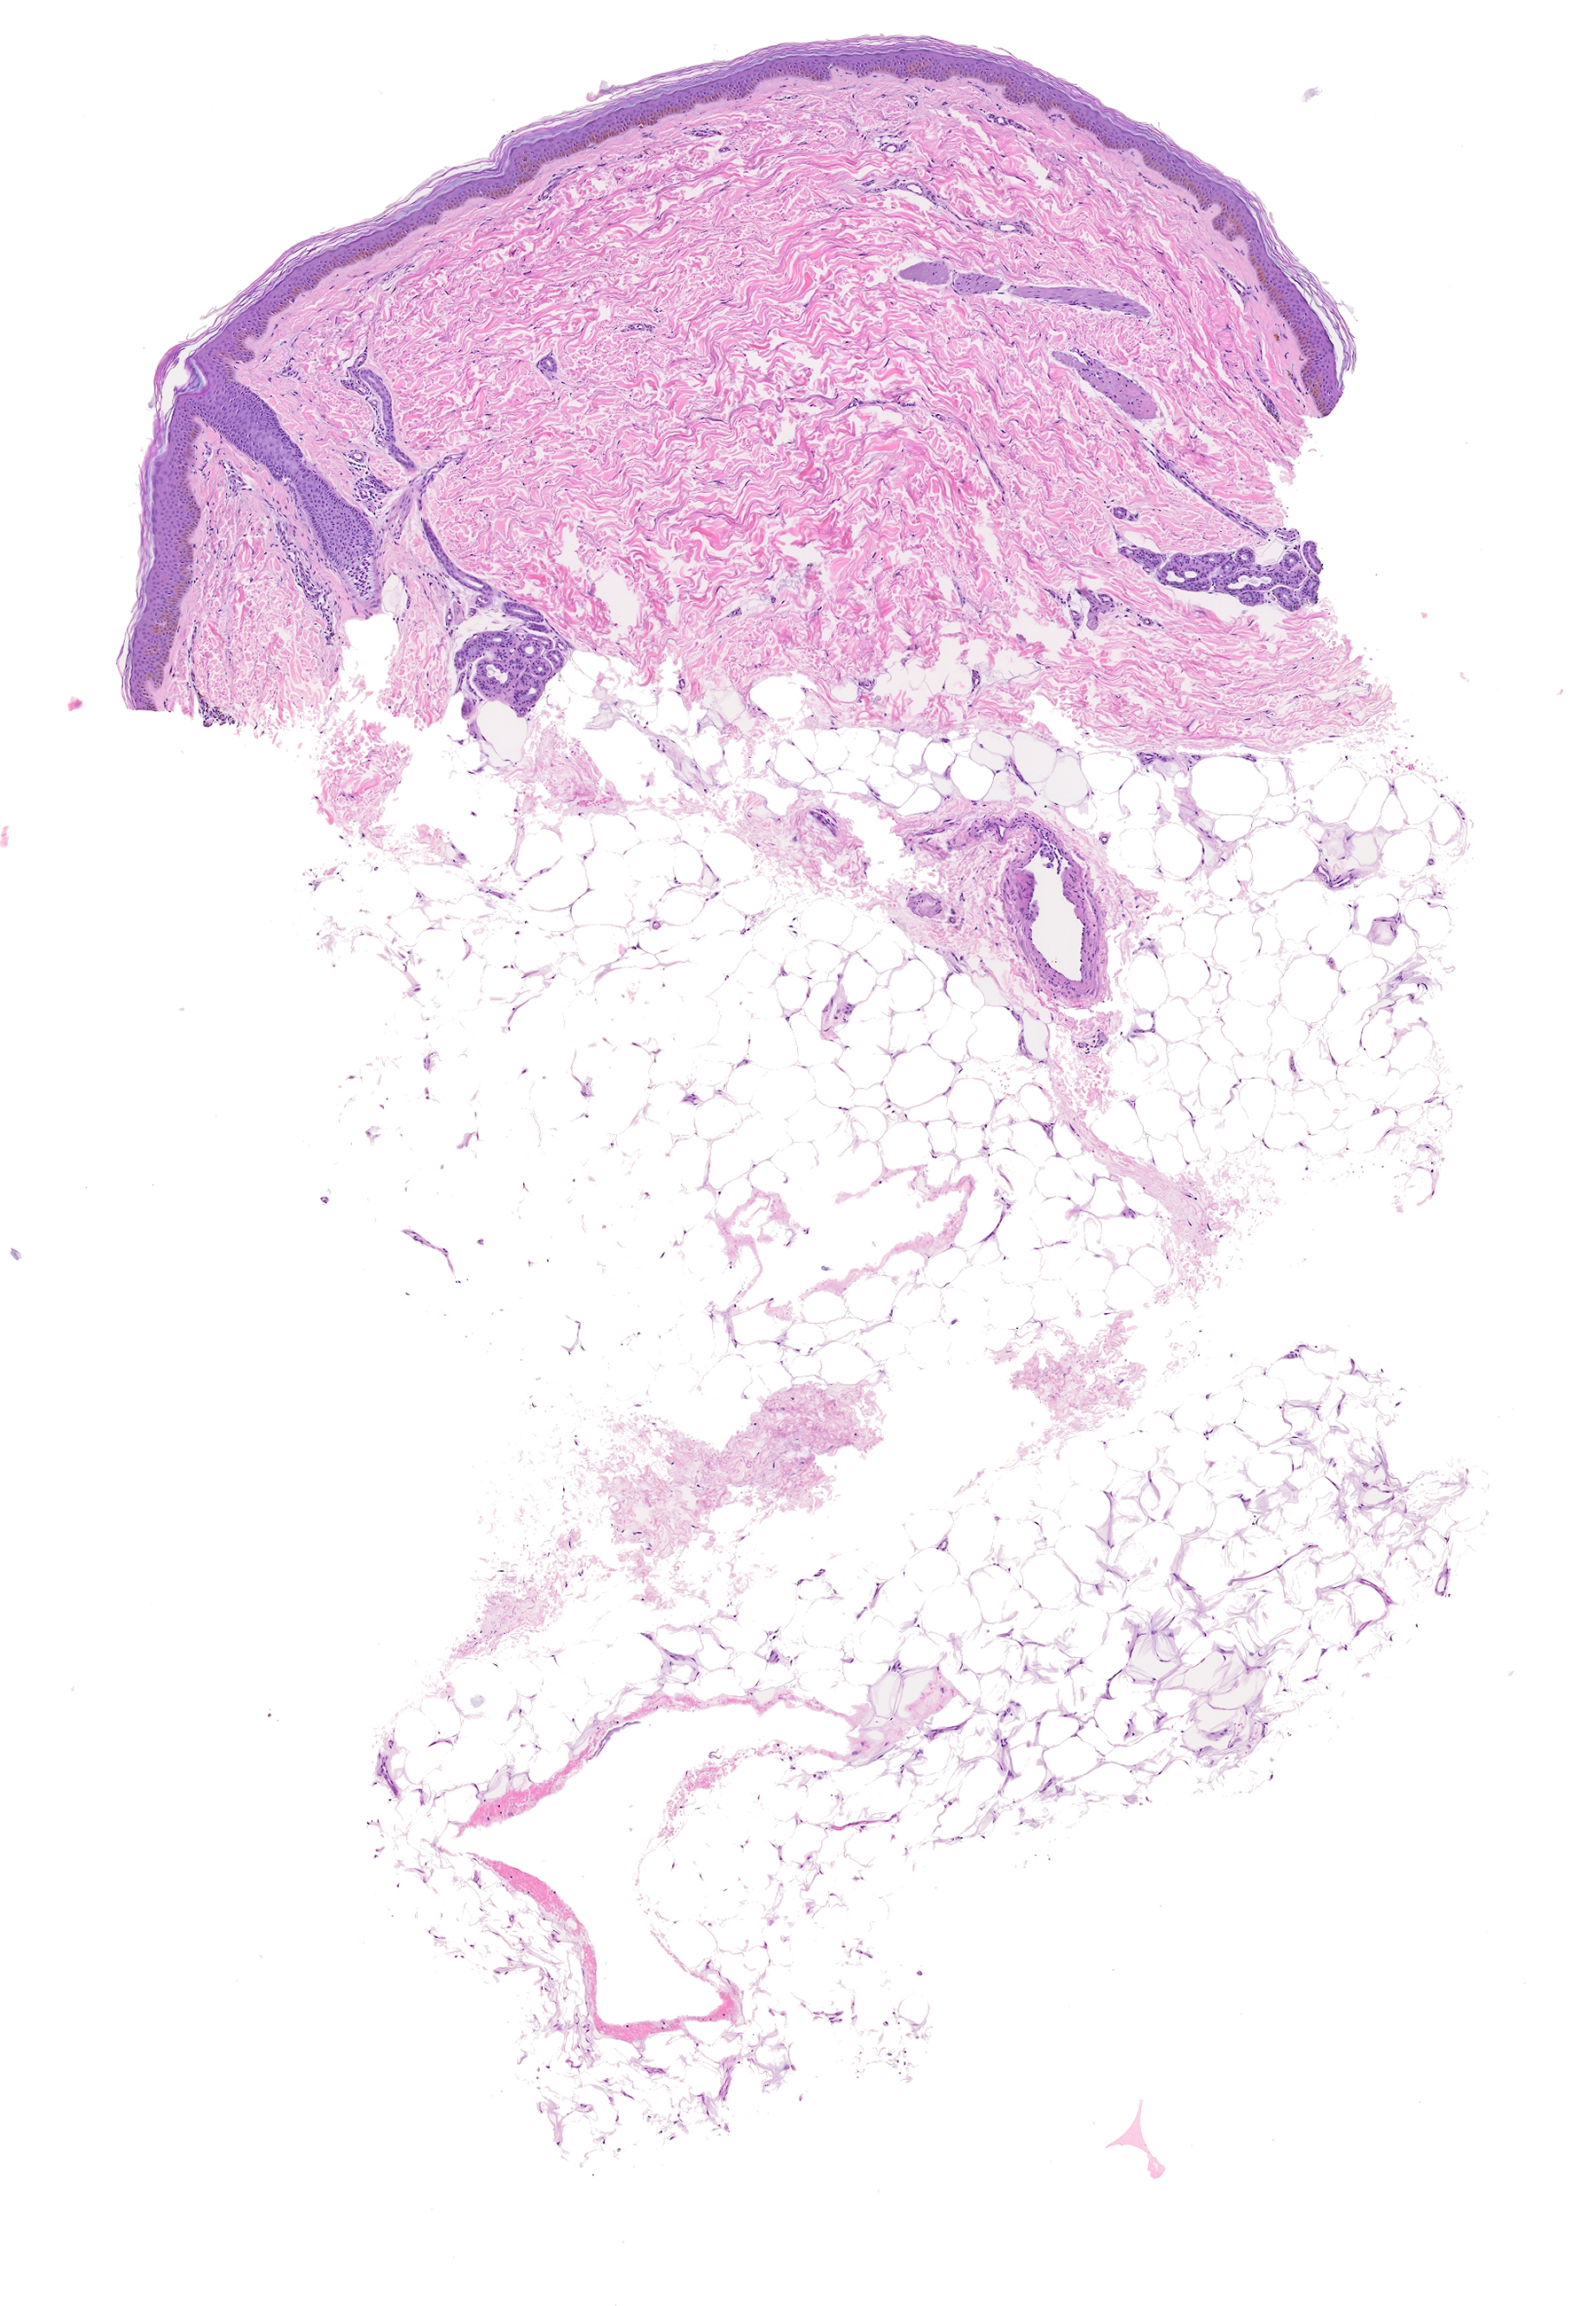

-Histología: Se practicaron dos biopsias cutáneas, una del tronco y otra de la extremidad superior de las que se muestran las tinciones de hematoxilina-eosina (Figuras 5 y 6) y de orceína (Figura 7).